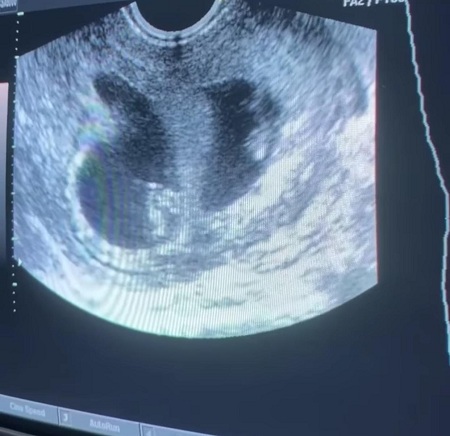

Esta estrella y Nick Cannon han anunciado a través del Instagram de Abby que están listos para traer a sus bebés gemelos a casa en 2021.

Abby De La Rosa había estado compartiendo fotos de su embarazo con sus fanáticos desde el 15 de diciembre de 2020.

Pero solo reveló quién era el papá del bebé el 12 de abril de 2021. Fue una sesión de fotos de maternidad.

En el pie de foto, la DJ mencionó lo agradecida que está por sus bebés y el hecho de que Abby no puede esperar para conocerlos.

También hay una iniciativa tomada por Abby llamada “Club Tummy”. Es como un DJ para bebés por nacer. Rosa toca sus canciones alegres favoritas para los pequeños ángulos de su barriga.